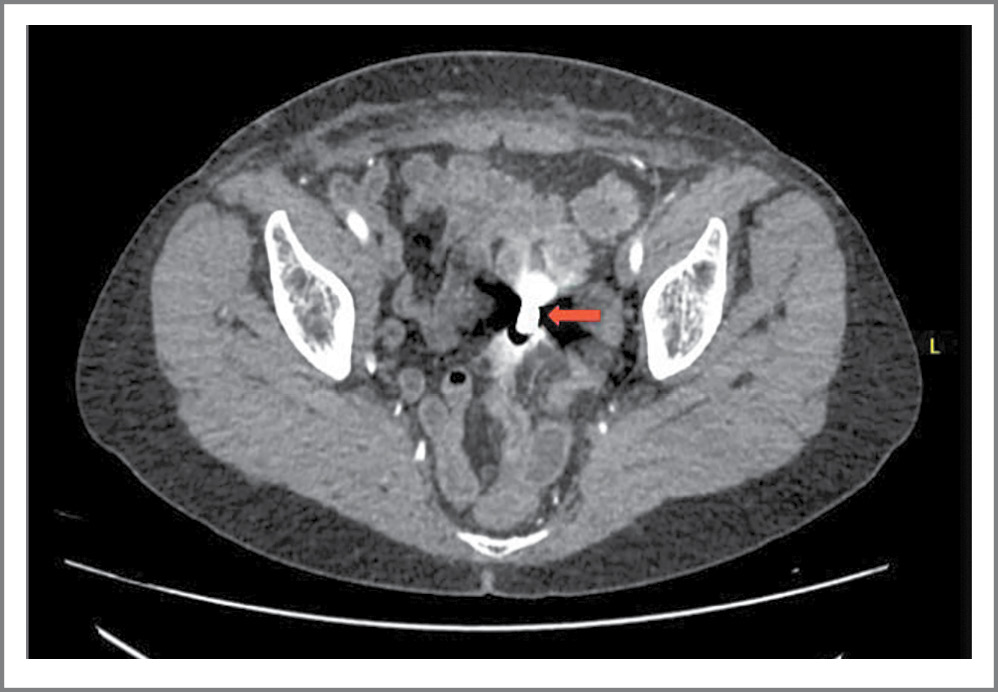

С целью исключения рецидива РТМ пациентке выполнены КТ органов грудной, брюшной полостей и МТ с контрастированием, колоноилеоскопия. В прямой кишке выявлены единичные телеангиоэктазии – проявления постлучевого проктита. По данным КТ во всех отделах визуализирована ТК. Рельеф ее СО сохранен. В МТ в средних петлях ТК визуализирован сегмент с суженным просветом до 1–2 мм, протяженностью до 40 мм, с циркулярно утолщенными до 5 мм стенками (рис. 1).

Рис. 1. КТ брюшной полости. Постлучевая стриктура тощей кишки.

Fig. 1. Abdominal CT scan. Post-radiation stricture of the jejunum.

Отмечено некоторое повышение накопления контрастного препарата стенками кишки на этом уровне. Проксимальнее описанной зоны определено инородное тело плотностью 14000 HU – видеокапсула (рис. 2).

Рис. 2. КТ брюшной полости. Видеокапсула в просвете тощей кишки.

Fig. 2. Abdominal CT scan. Video capsule in the lumen of the jejunum.